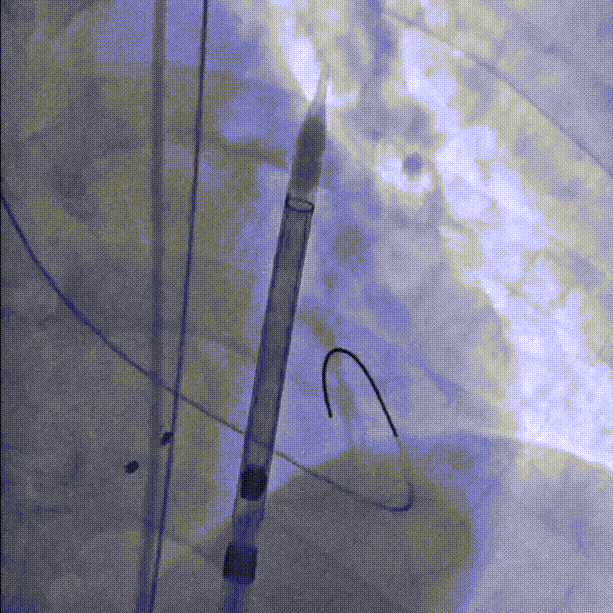

球囊预扩张:

初始定位,左右窦重叠视图开始释放:

释放中期,快速起搏下释放到80%切换视图,并借助食管心超评估深度和反流情况: